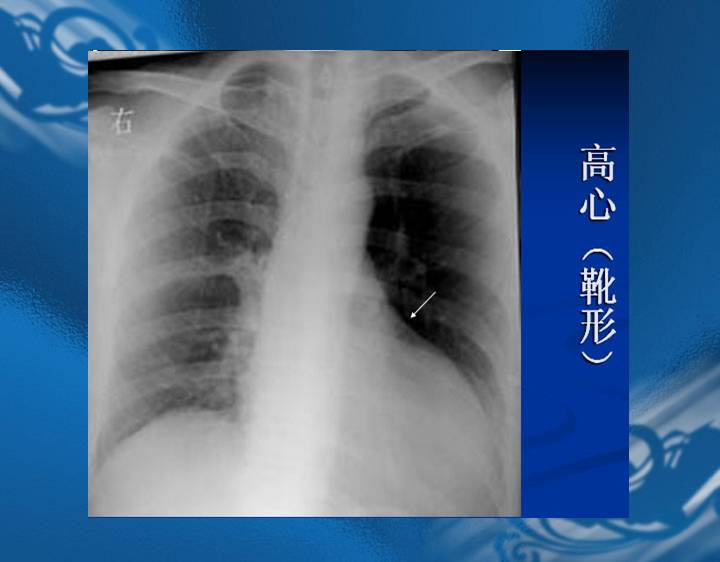

执业医师资格考试“实践技能”影像学辅导资料